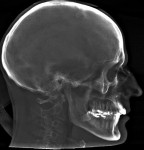

In the case presented, a 59-year-old male patient had severe OSA (AHI 45), decreased posterior airway space, and concomitant maxillofacial skeletal deformities (Angle class II malocclusion, maxillary and mandibular retrognathia, transverse maxillary hypoplasia, and transverse mandibular hypoplasia) (Figure 1 through Figure 4). Orthognathic surgical planning included tracings of a reconstructed lateral cephalogram to estimate postsurgical esthetic changes after advancements of 8 mm, 10 mm, and 12 mm (Figure 5). It is important to note that facial esthetics may change significantly, and this must be discussed in detail with the patient.

The patient is then awakened and sent to either the intensive care unit overnight or the surgical floor, depending on any preoperative comorbidities and the operative course. Hospital stay is generally 1 to 2 nights. A postoperative CBCT is taken on postoperative day 1. In the present case, the postoperative CBCT, as compared to a preoperative CBCT, demonstrated the successful results of the treatment (Figure 13 and Figure 14).